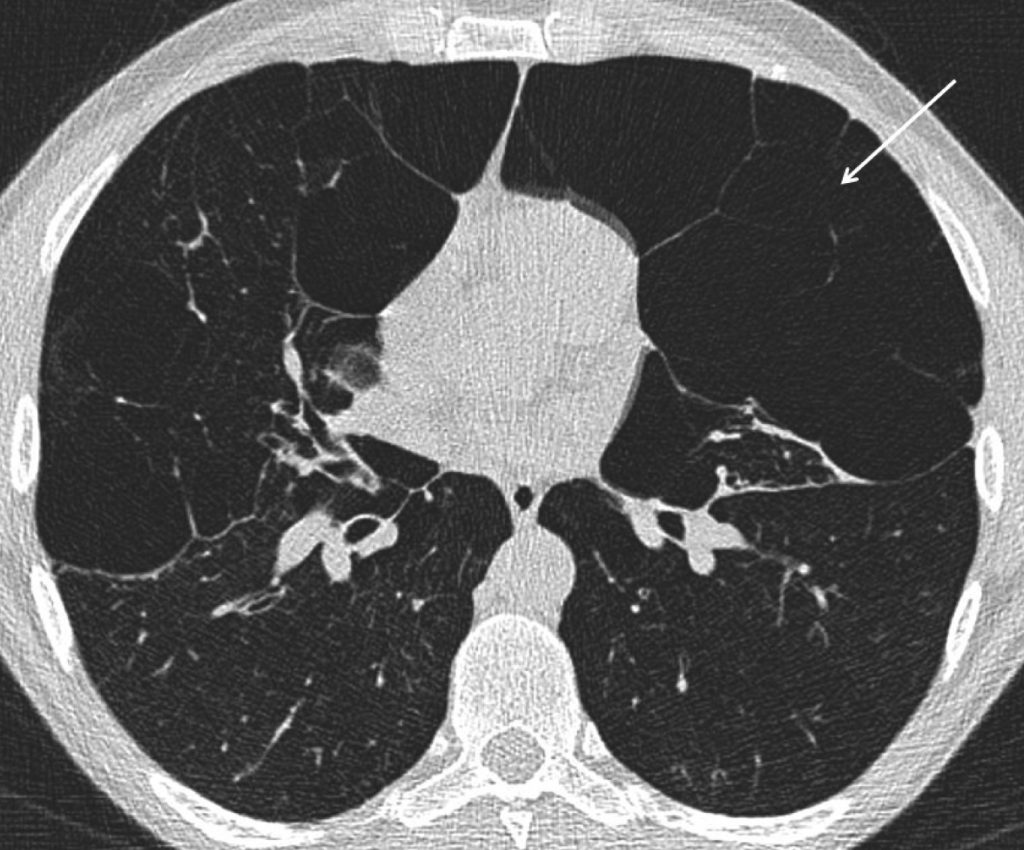

- La tomodensitométrie permet d’objectiver très précisément l’emphysème et le syndrome bronchique :

- l’emphysème se traduit par des plages hypodenses avasculaires qui correspondent à un remplacement du parenchyme pulmonaire par de l’air. La distribution lésionnelle est variable, généralement à prédominance apicale dans l’emphysème centrolobulaire, plus diffuse dans l’emphysème panlobulaire (figure 90.2) ;

Fig. 90.2 Scanner thoracique. Coupe axiale.

Emphysème panlobulaire traduit par des plages hypodenses avasculaires (flèche) correspondant à une destruction du parenchyme pulmonaire.

Source : CERF, CNEBMN, 2022.